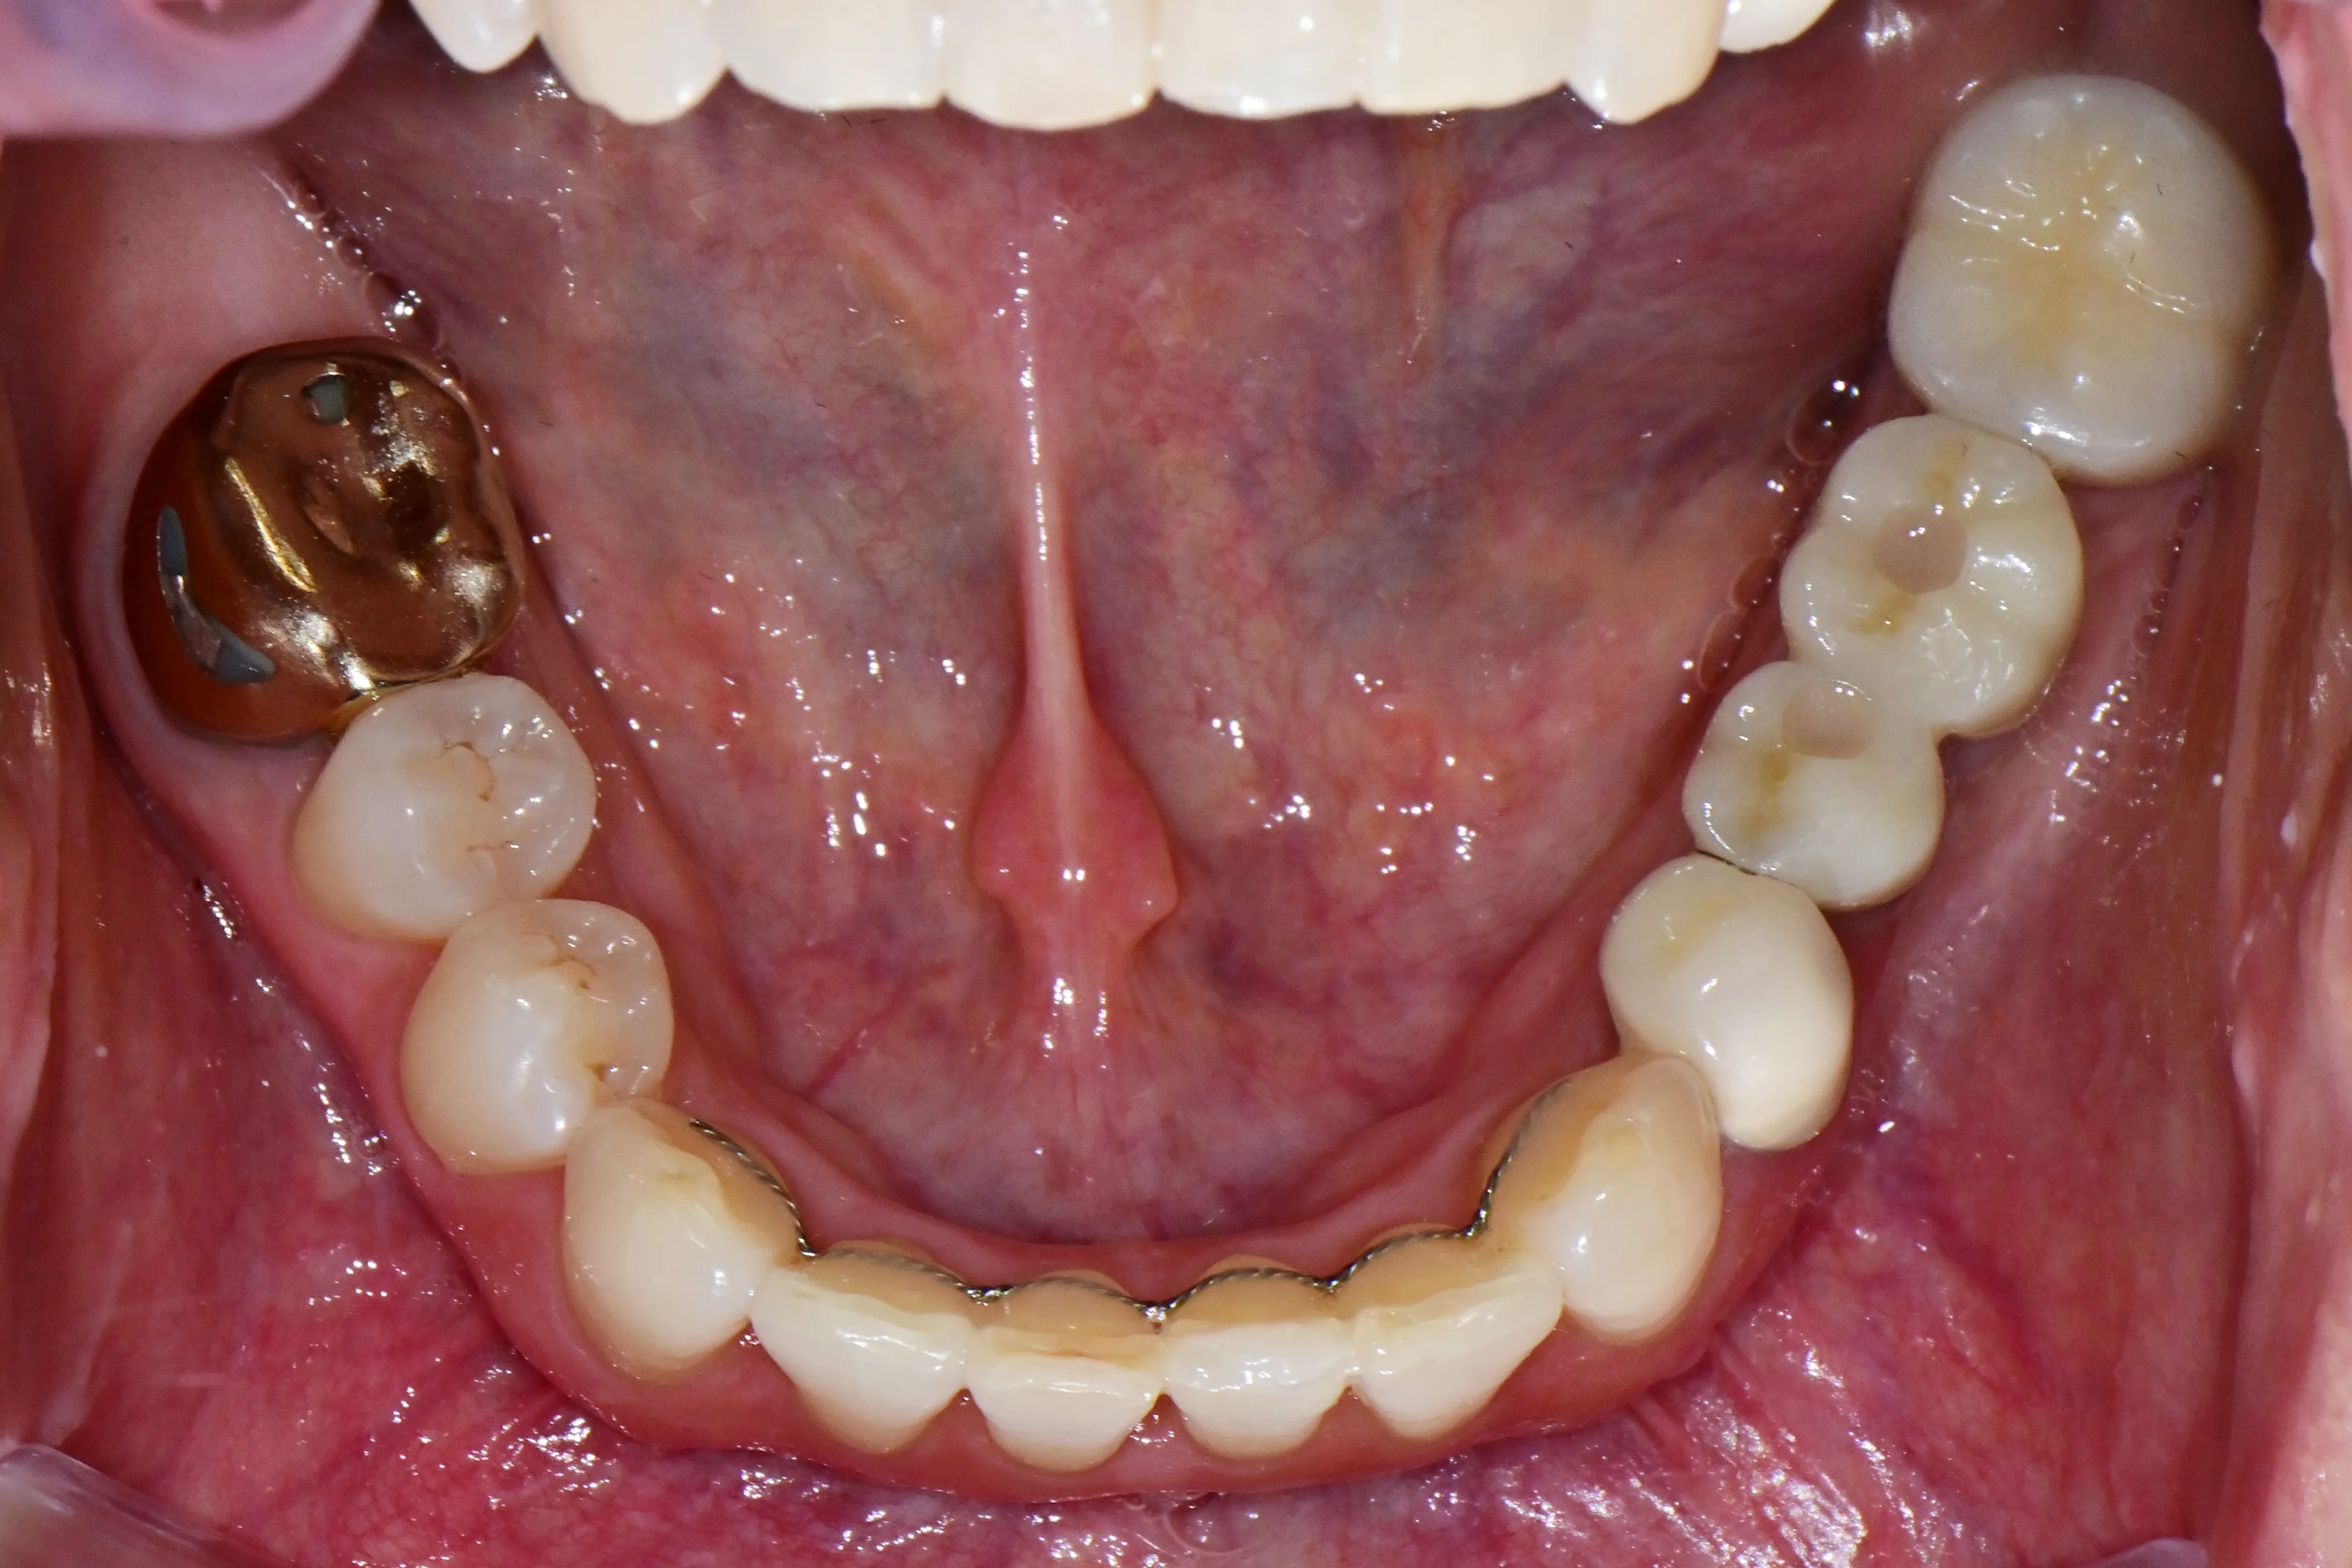

이 환자분은 이미 구강 안에 여러 개의 임플란트와 브릿지 보철물이 있는 상태였습니다. 앞니는 가지런하지 않고, 윗니가 아랫니를 깊게 덮는 과개교합(deepbite)도 있었습니다. 이런 경우 가장 중요한 것은 기존 임플란트와 보철물의 교합을 그대로 유지하면서, 나머지 치아만 가지런하게 배열하는 것입니다.

인비절라인의 디지털 치료 계획을 활용해서, 임플란트와 보철물이 있는 어금니는 움직이지 않도록 고정하고 앞니 위주로만 이동시켰습니다. 덕분에 발치 없이, 고무줄이나 미니스크류 같은 추가 장치 없이도 15개월 만에 치료를 마무리할 수 있었습니다.

보철물이나 임플란트가 많다고 교정이 어려운 것은 아닙니다. 오히려 이를 고정원으로 활용하면 치료 효율이 높아지는 경우도 있습니다.